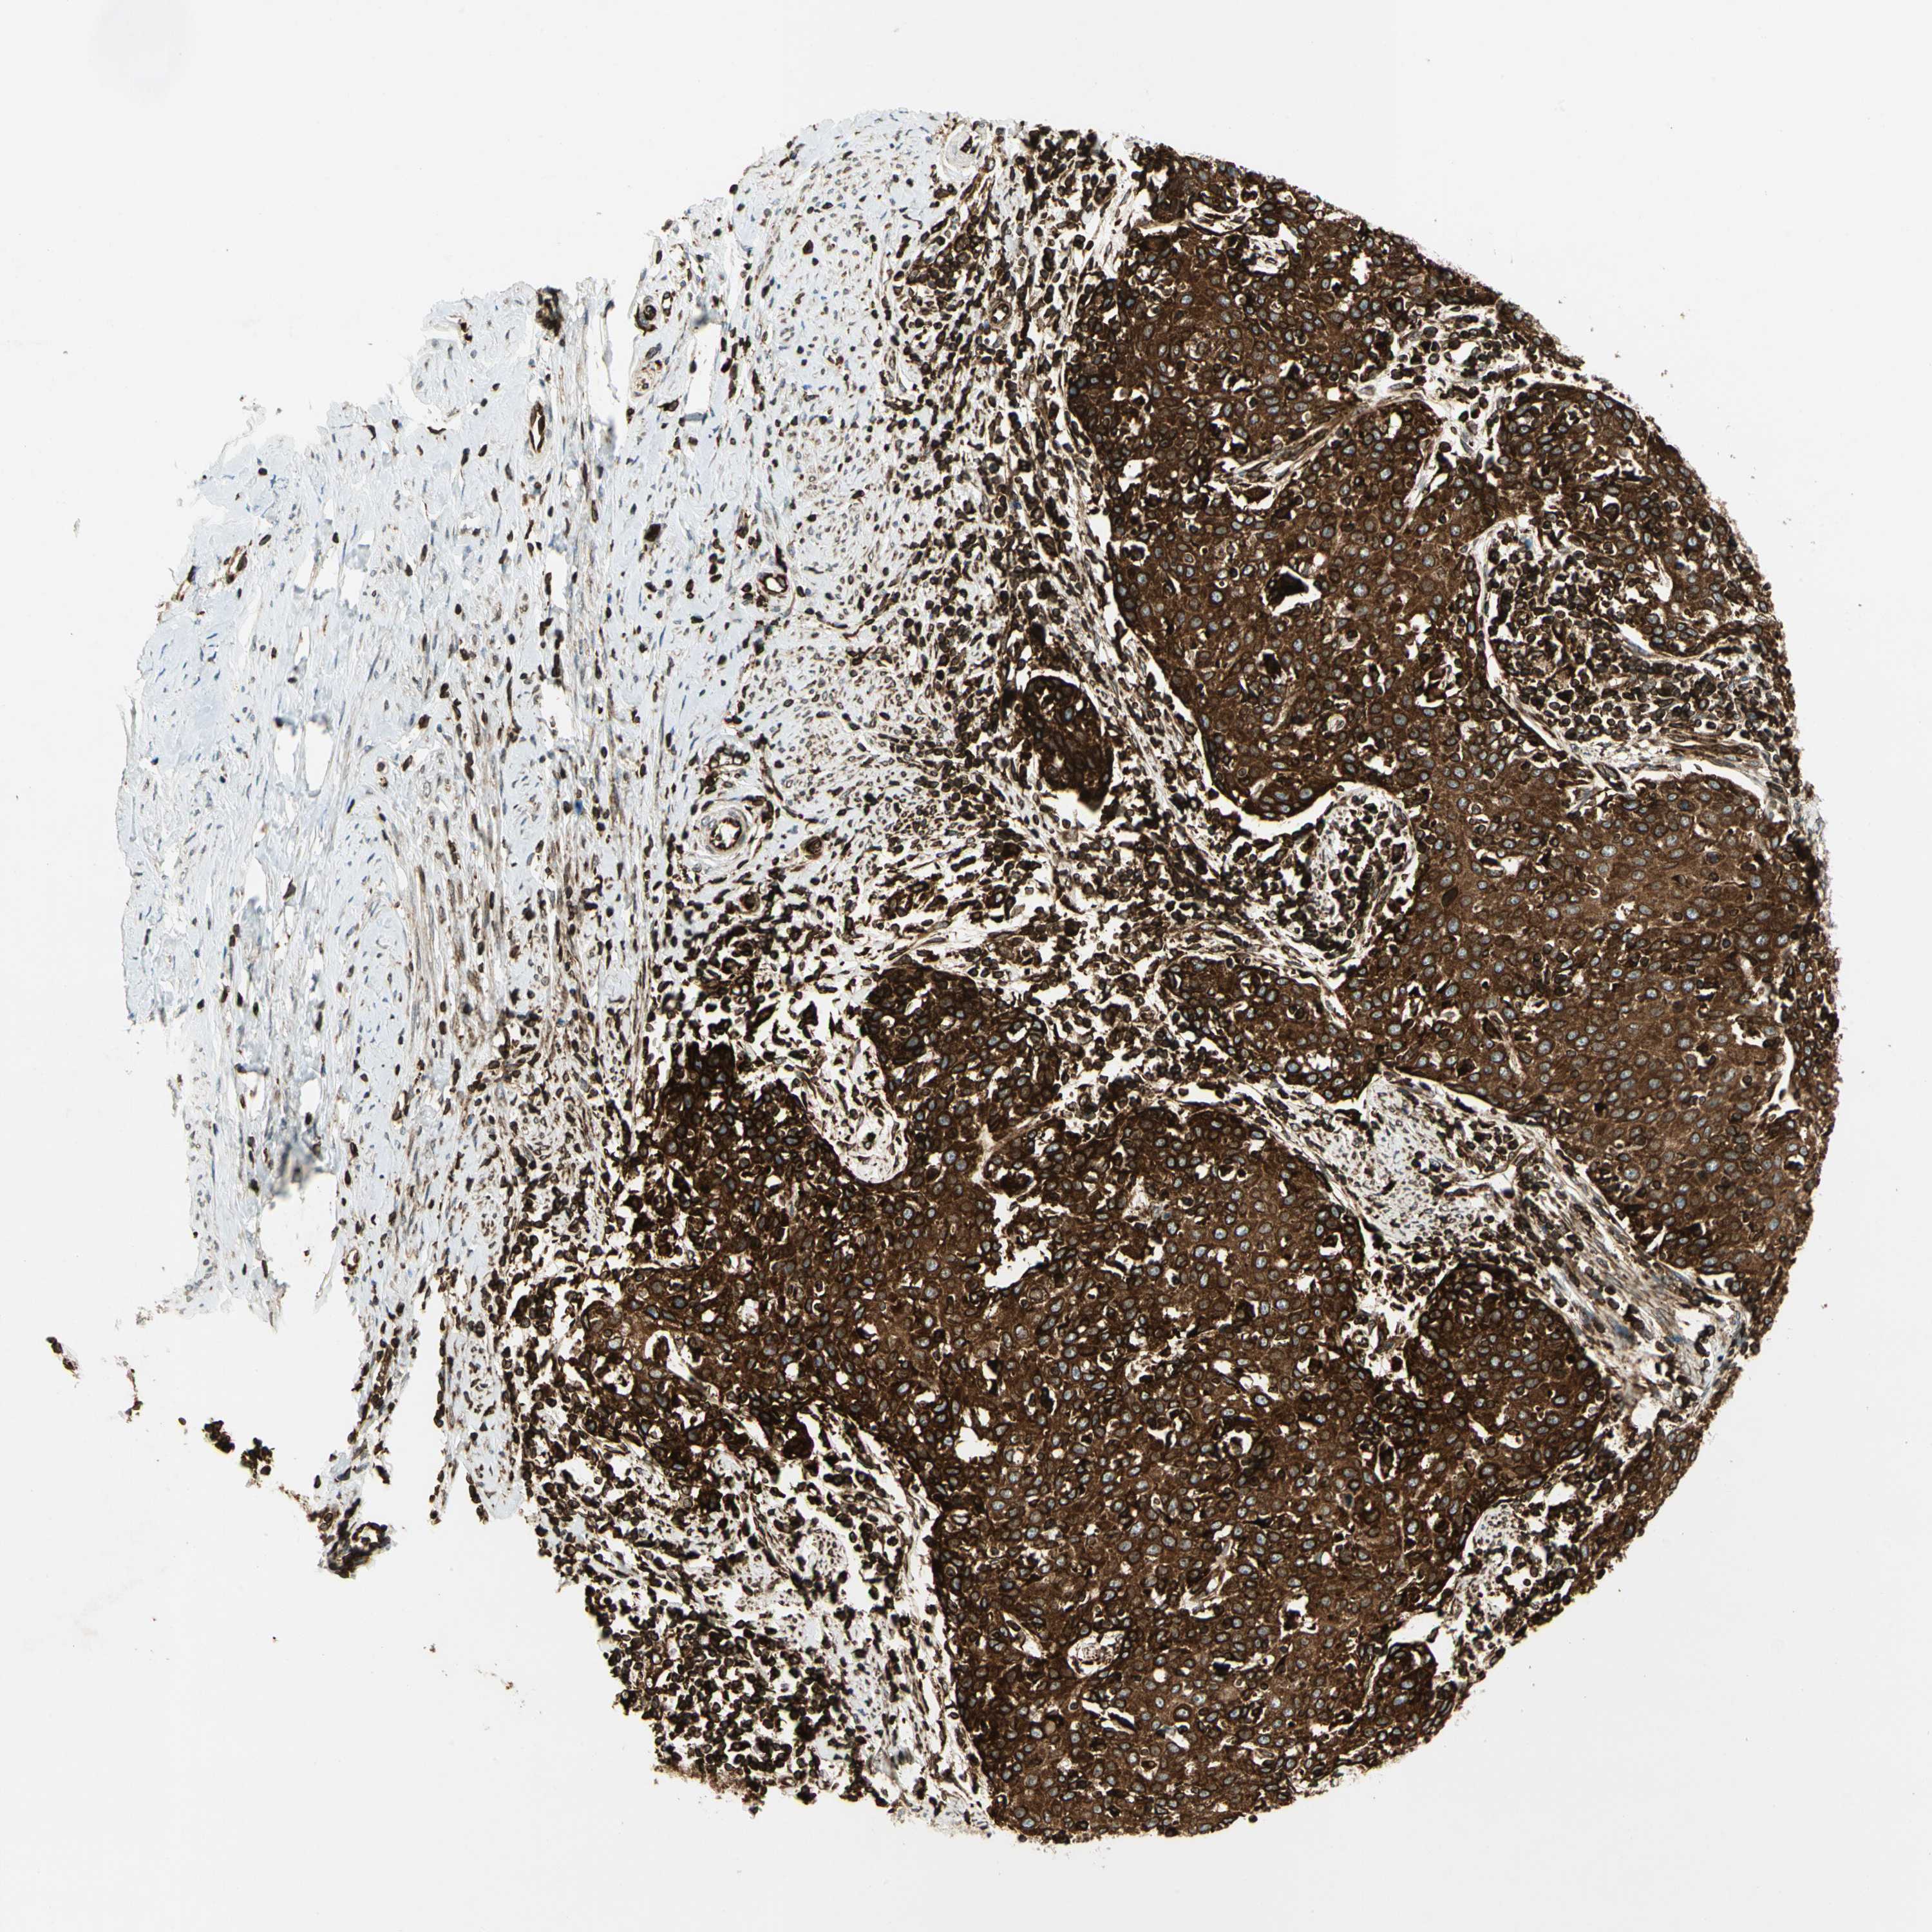

CERVICAL CANCER - Protein expressioni

A mouse-over function shows sample information and annotation data. Click on an image to view it in a full screen mode. Samples can be filtered based on level of antibody staining by selecting one or several of the following categories: high, medium, low and not detected. The assay and annotation is described here.

Note that samples used for immunohistochemistry by the Human Protein Atlas do not correspond to samples in the TCGA dataset.

Antibody stainingi

Antibody staining in the annotated cell types in the current human tissue is reported as not detected, low, medium, or high, based on conventional immunohistochemistry profiling in selected tissues. This score is based on the combination of the staining intensity and fraction of stained cells.

Each image is clickable and will lead to virtual microscopy that enables deeper exploration of all samples and also displays staining intensity scores, fraction scores and subcellular localization as well as patient and tissue information for each sample.

Antibody HPA007066

Staining

High

Medium

Low

Not detected

Intensity

Strong

Moderate

Weak

Negative

Quantity

>75%

75%-25%

<25%

None

Location

Nuclear

Cytoplasmic/membranous

Cytoplasmic/membranous,nuclear

Squamous cell carcinoma, NOS

Adenocarcinoma, NOS